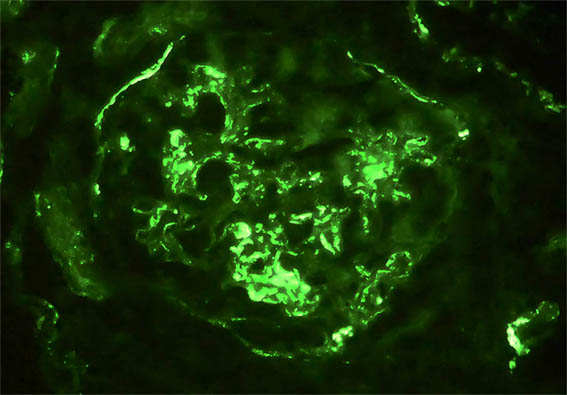

Se hace biopsia del injerto renal, observe las imágenes.

Figura 11. Inmunofluorescencia para IgA, X400. Positividad mesangial y subendotelial.

Figura 12. Inmunofluorescencia para IgM, X400. Positividad mesangial y subendotelial.

Inmunofluorescencia directa para IgG y C1q: Negativas; kappa y lambda: Tinción similar a la de IgA e IgM. C4d: negativo.